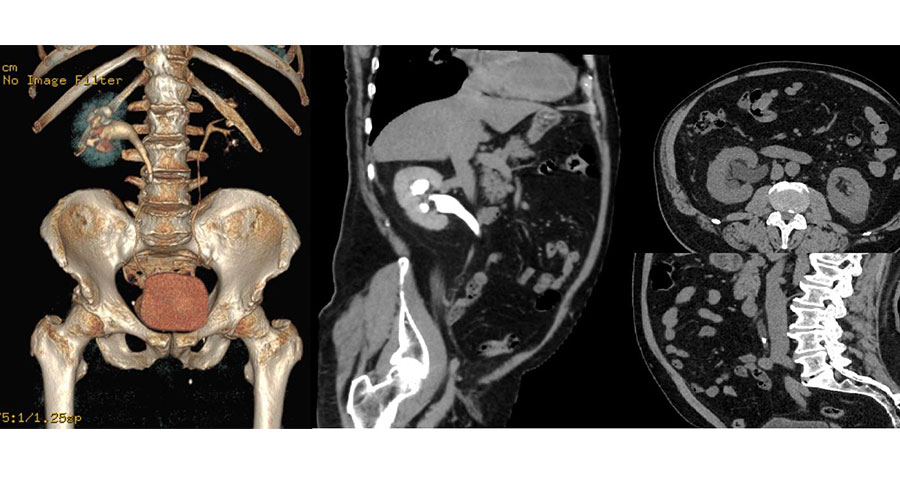

URO-CT sau urografia prin tomografie computerizată este o investigație medicală imagistică folosită pentru a evalua tractul urinar al unei persoane.

Tractul urinar include rinichii, ureterele (tuburile care transportă urina de la rinichi la vezică) și vezica urinară.

„URO-CT-ul este considerat o evaluare superioară față de urografia clasică, deoarece oferă imagini mai detaliate și poate detecta o gamă mai largă de afecțiuni. Investigația folosește o combinație de raze X pentru a genera imagini în secțiune ale rinichilor, ureterelor și vezicii urinare. Procedura este non invazivă, iar rezultatele se pot obține foarte repede, ceea ce permite începerea unui potențial tratament într-un interval de timp foarte scurt. Pentru a capta imagini și mai clare, se utilizează, de obicei, o substanță de contrast iodată, care este injectată în venă înaintea scanării”, spune asist. univ. Emil Stoicescu – Radiologie si imagistică medicală – Spitalul Victor Babeș Timișoara.

„Este important de menționat că, înainte de a efectua o tomografie computerizată urologică, se vor lua în considerare factorii individuali ai pacientului, inclusiv istoricul medical, simptomele, dar și alte investigații anterioare. Imaginile obținute prin URO-CT furnizează informații legate de extinderea și localizarea precisă a unei afecțiuni, ceea ce permite stabilirea unui plan terapeutic pentru fiecare pacient în parte. De exemplu, în cazul pietrelor la rinichi, dimensiunea și localizarea acestora pot influența decizia cu privire la intervenția chirurgicală sau la alte metode de tratament. De asemenea, cu ajutorul acestui screening poate fi apreciată si calculată densitatea calculului reno-urinar. Datorită capacității sale de a evidenția chiar și cele mai mici modificări ale țesuturilor și structurilor anatomice, URO-CT-ul poate contribui la detectarea precoce a afecțiunilor urologice”, mai spune spune asist. univ. Emil Stoicescu.